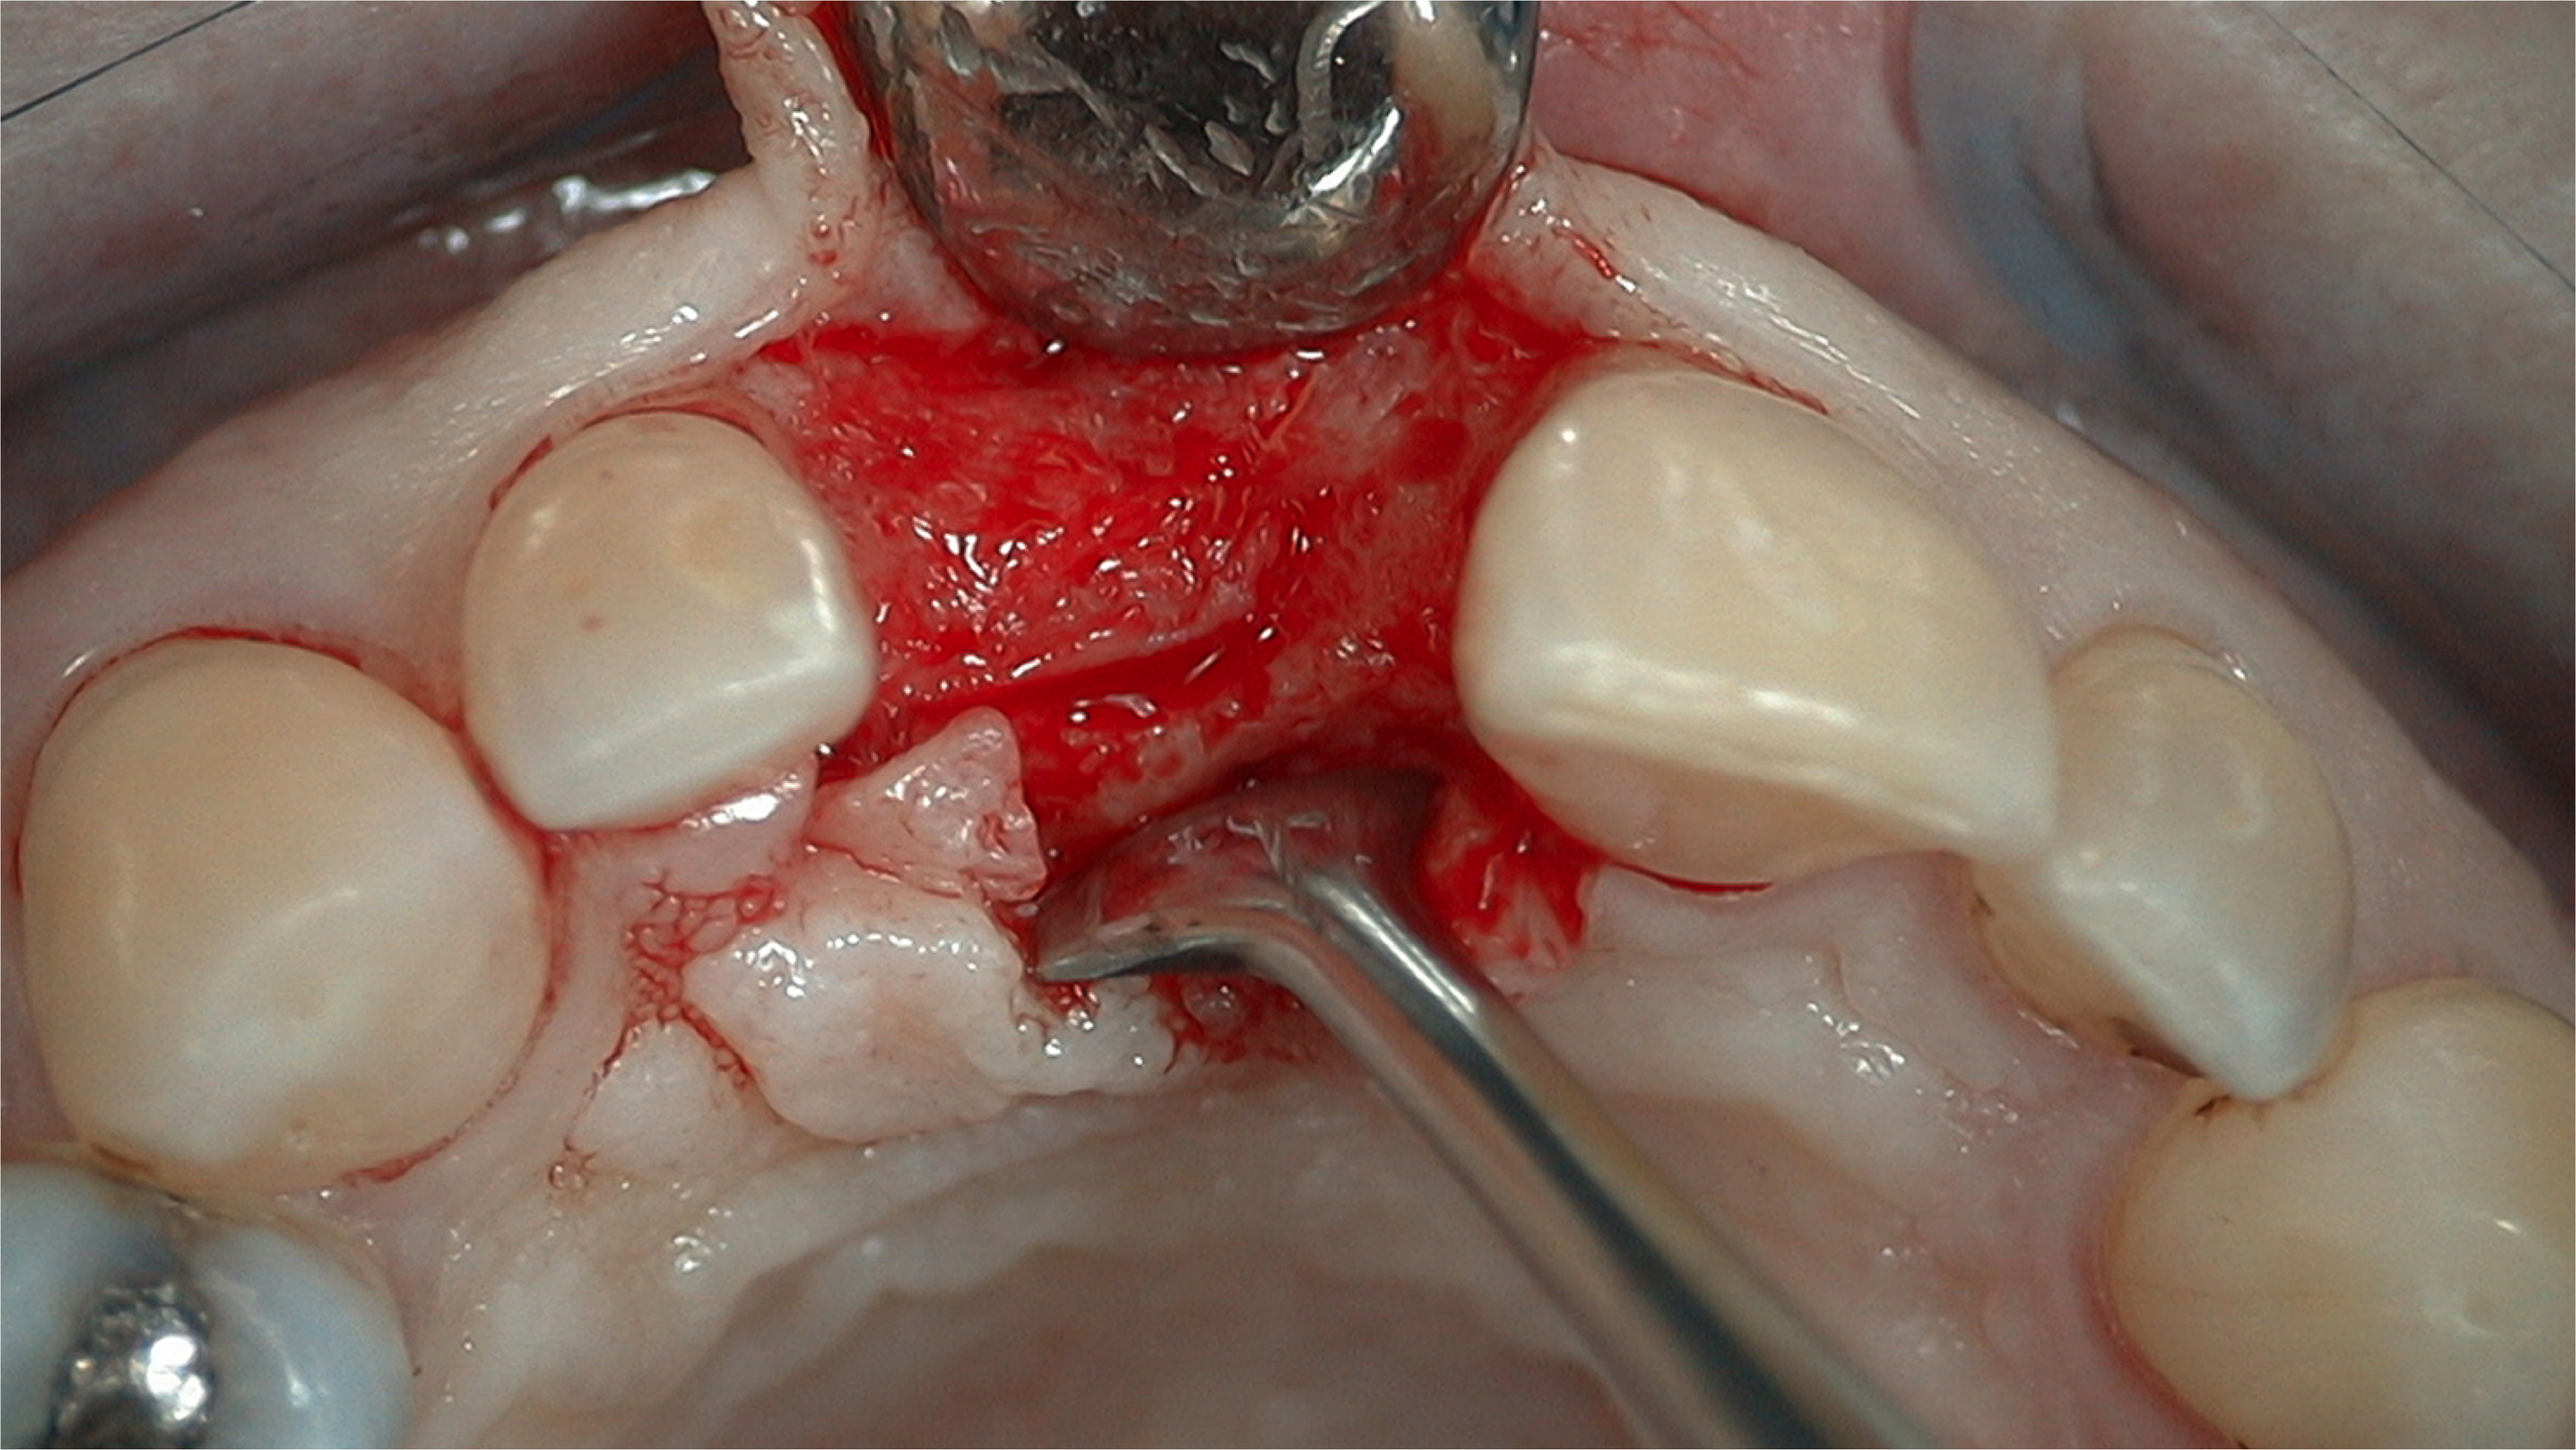

A flap procedure reveals the bone, which should be wide enough to provide 1.5 mm of bone on either side of the implant (Figure 5).6 The amount and level of bone surrounding implants is important for osseointegration, esthetics, and long-term survival.6 The location for implant placement can then be established using a round bur to place a mark in the center of the crest of bone from mesial-distally and facial-palatally (Figure 6).

Fig 5. 1.5 mm of bone should surround the implant on either side.

Figure 5

Fig 6. The location for implant placement can then be established using a round bur.

Figure 6